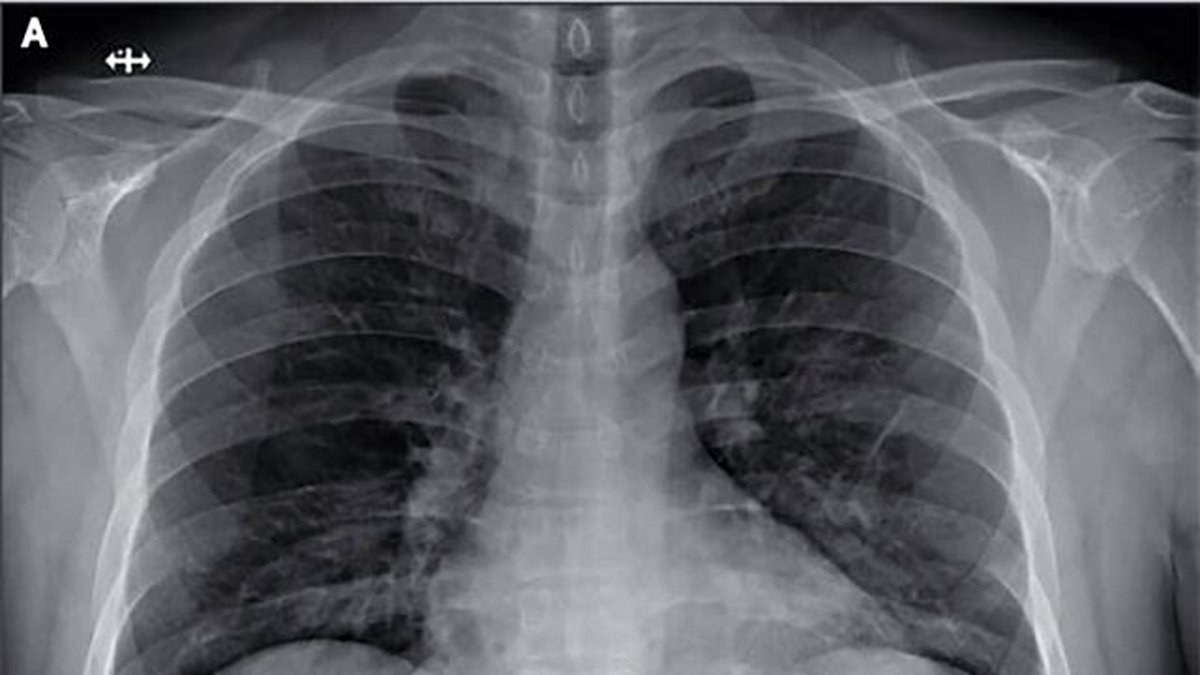

وی با اشاره به نشانههای بیماری، ادامه داد: سرفههای خشک، گلودرد، تب، بدن درد، ایجاد تغییر در حس بویایی و چشایی و در برخی از مواقع، علائم گوارشی و پوستی از نشانههای بیماری است؛ اما آنچه مهم است و میتواند منجر به موارد شدید و بحرانی بیماری شود، هویدا شدن نشانههایی است که بافت ریه را به شکل شدید درگیر کرده یا اصطلاحا بیمار دچار ذاتالریه شده و به دنبال واکنش ریه فرد ممکن است دچار زجر تنفسی شود.این عضو هیئت علمی دانشگاه شهید بهشتی، افزود: به دنبال بروز سندروم زجر تفسی برخی عوامل التهابی و مایعی حاوی پروتئین وارد کیسههای هوایی شده و سبب پر شدن این کیسههای هوایی خواهد شد. این پاسخ التهابی زیاد از سوی ریه میتواند سبب شود اکسیژن نتواند وارد کیسههای هوایی شود و در نتیجه اکسیژن خون کاهش مییابد.